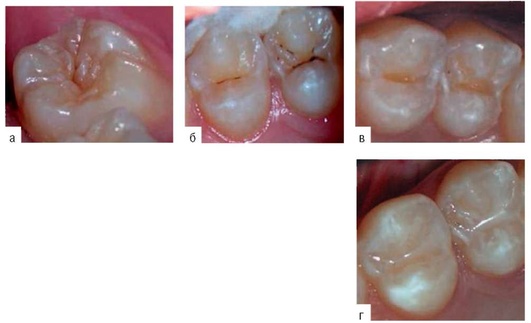

При проведении инвазивной герметизации чаще используют композиционные герметики (рис. 22-4). После очистки зуба расширяют вход в фиссуру с помощью алмазных копьевидных боров путем снятия твердых тканей в области стенок фиссур. После расшлифовки дно и стенки фиссуры должны быть доступны для осмотра, а твердые ткани - плотными при зондировании.

При проведении инвазивной герметизации рекомендуют использовать только композиционные герметики, но возможно применение с этой целью и жидкотекучих композитов.

Профилактическое пломбирование

Показания :

Особенности технологии

Кариозные полости обрабатывают конусовидными и небольшими шаровидными борами, удаляют только деминерализованные ткани. В качестве профилактических пломб используют различные пломбировочные материалы (СИЦ, компомеры, композиты).

Выбор пломбировочных материалов зависит от глубины кариозной полости, уровня минерализации твердых тканей зуба и характера течения кариозного процесса.

В зубах со зрелой эмалью при поверхностном и среднем (благоприятно протекающем) кариесе рекомендуют использовать композиционные герметики и жидкотекучие композиты. Кариозные полости пломбируют жидкотекучими композитами; материал помещают чуть ниже краев кариозной полости; сверху наносят герметик.

Методика проведения

-

Тщательно очищают жевательную поверхность с помощью абразивных паст и осуществляют диагностику состояния фиссур.

-

Кариозные полости препарируют конусовидными и небольшими шаровидными борами, удаляют только деминерализованные ткани. При наличии кариозной полости в пределах эмали используют композитные пломбы.

-

Вносят жидкотекучий композит (пломбировочный материал помещают чуть ниже краев кариозной полости), фотополимеризируют.

-

Удаляют протравочный агент с помощью струи воды. Высушивают зуб.

-

На область пломбы и прилегающие фиссуры наносят слой композиционного наполненного герметика и фотополимеризируют.

При лечении фиссурного кариеса в зубах с незрелой эмалью, с учетом имеющейся исходной гипоминерализации твердых тканей прорезывающихся зубов и активного течения кариозного процесса, в качестве профилактической пломбы используют жидкотекучие компомеры («Dyract Flow», «Compoglass Flow») и ком-померные герметики («Dyract Seal»). В таких случаях в качестве адгезивных систем используют щадящие самопротравливающие системы, например «Prime&Bond NT» c NRC кондиционером.

Возможны варианты сочетания пломб и СИЦ или компомера и композиционного герметика (рис. 22-5).

По нашим наблюдениям, полная сохранность профилактических пломб после двух лет наблюдения составляла 96%. В 4% случаев отмечена частичная убыль композиционного герметика.

Вышеописанный алгоритм профилактики фиссурного кариеса позволяет получить 100% редукцию кариеса фиссур к 12-летнему возрасту.